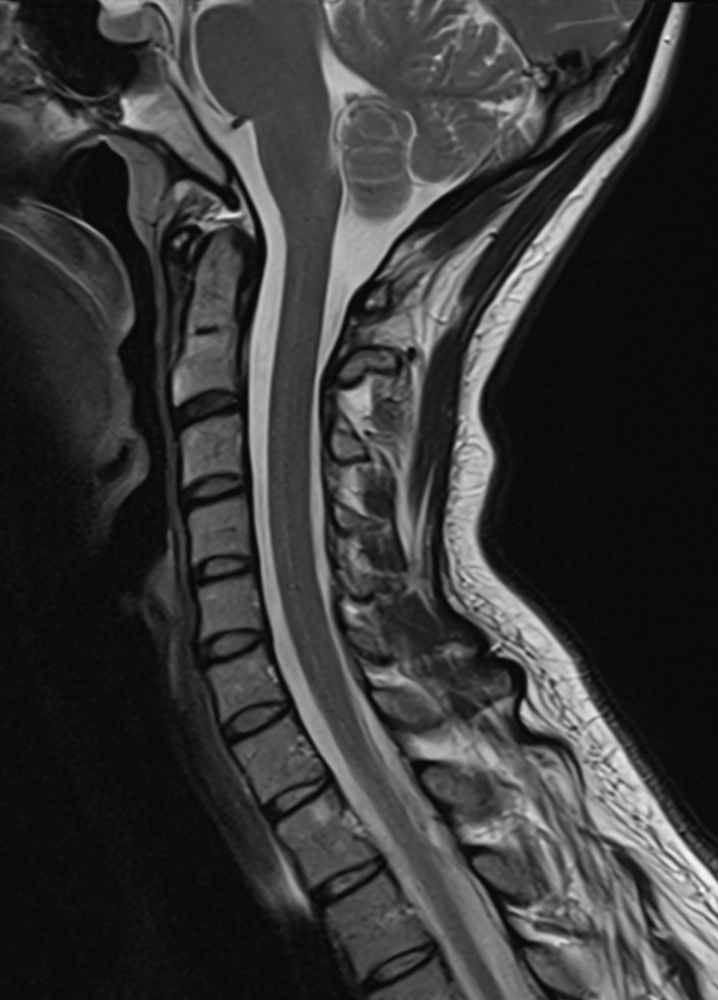

MRT der Wirbelsäule

Zur Untersuchung von Rückenproblemen, insbesondere im Fall von Bandscheibenvorfällen und Verschleißerkrankungen hat sich die Magnetresonanztomographie als äußerst nützliches diagnostisches Verfahren etabliert. Die MRT ermöglicht eine präzise Darstellung der Wirbelsäule einschließlich der Bandscheiben, Wirbelkörper und Nervenwurzeln. Dadurch können etwa Bandscheibenvorfälle erkannt werden. Bei einem Bandscheibenvorfall verändert die weiche Bandscheibe zwischen den Wirbeln ihre Position und verursacht, indem sie auf Nerven drückt, Schmerzen und Beschwerden. Auch Verschleißerkrankungen wie Arthrose der Wirbelsäule oder entzündliche Erkrankungen (sogenannte Spondylarthritis) können durch die MRT diagnostiziert werden. Ihr behandelnder Arzt kann dadurch den Grad der Degeneration und damit auch die entsprechenden möglichen Behandlungsansätze beurteilen.